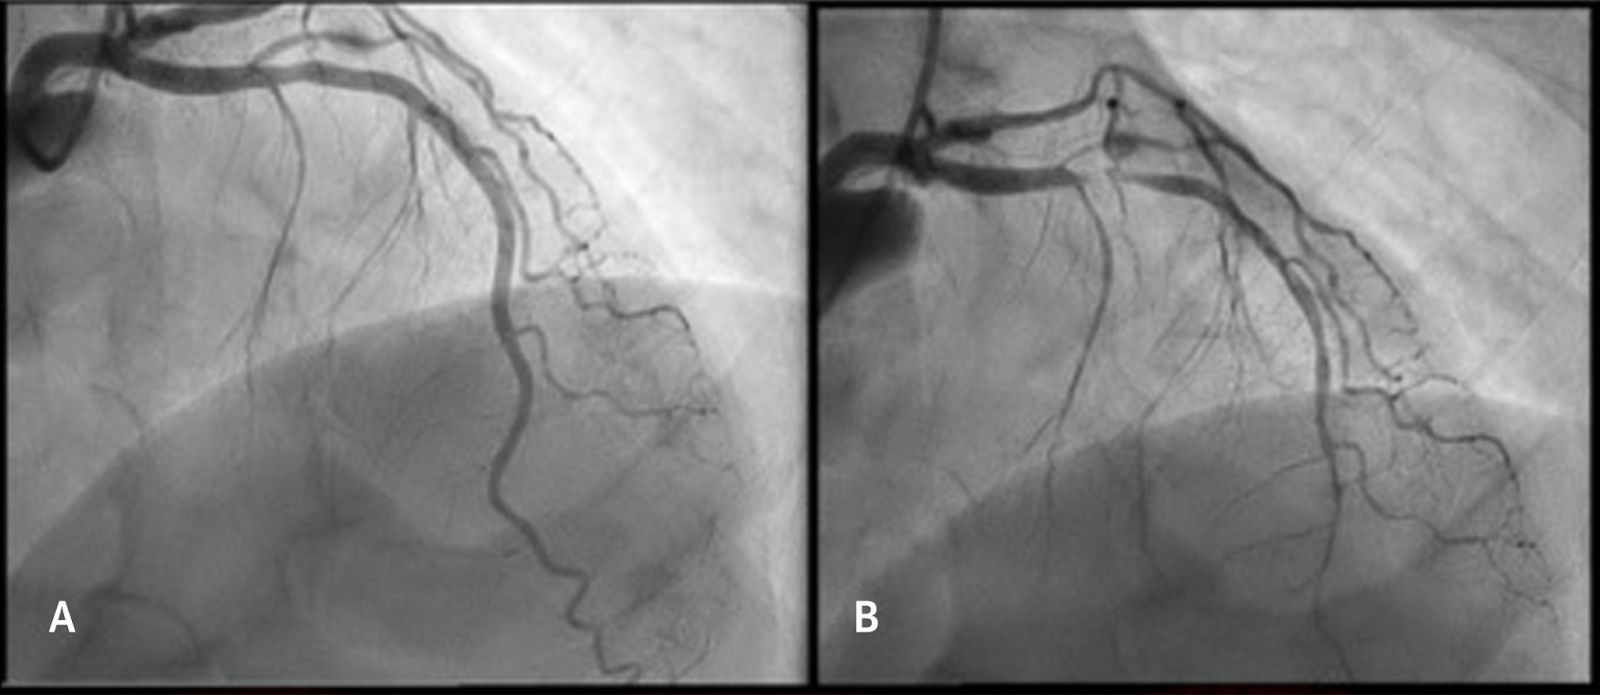

Como o tema da semana é vasoespamo, destacamos a imagem do próprio artigo de revisão sobre vasoespasmo e ateroesclerose. À esquerda: ADA com lesão focal discreta; À direita: lesão focal suboclusiva após administração de acetilcolina.

No artigo há, ainda, a imagem de OCT dessa placa que angiograficamente passa-se quase imperceptível. Vale a pena conferir!